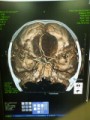

今日のお題はこれ! タイトルと本文を修正して日記を書いてみましょう。 BLS ACLS マスターなんとか。 あぁ面倒や。 新卒の子に、教える? どうせ講義は眠いと思うし。 うちの方が気疲れしてま... 続きを読む